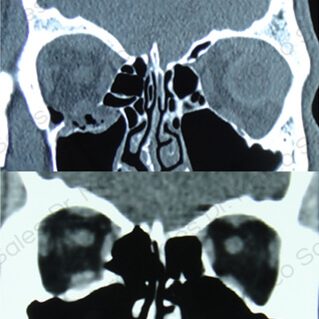

FRACTURAS ORBITARIAS